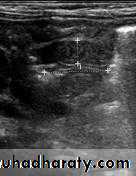

In a normal situation, the pyloric muscle thickness (diameter of a single muscular wall on a transverse image) should normally be less than 3 mm (most accurate 3) and the length (longitudinal measurement) should not exceed 15 mm.